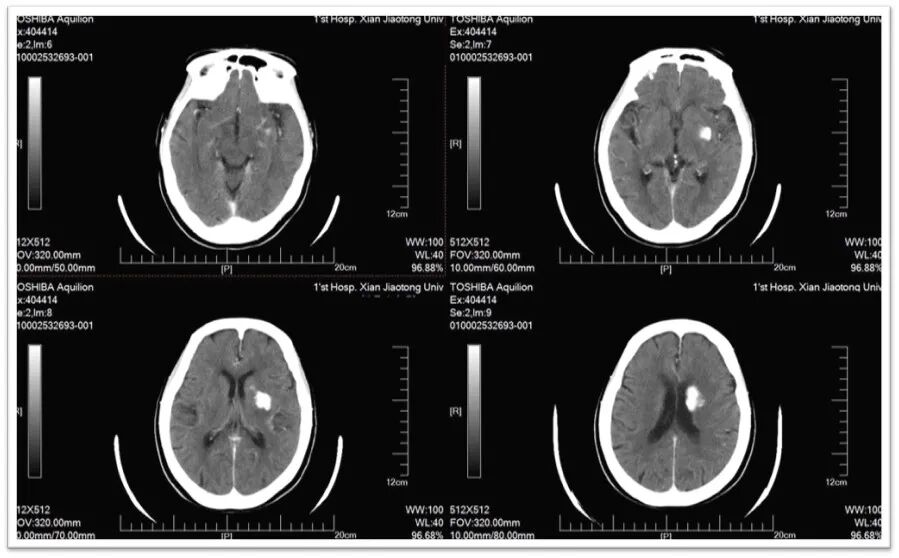

图1:头颅CT提示颅内多发腔隙性脑梗死,脑萎缩;